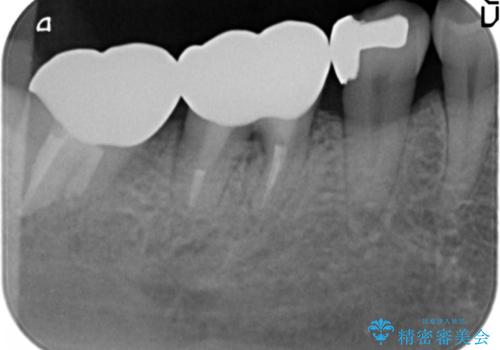

歯ぐきの腫れが治らない 石灰化した狭小根管治療

- 他院で根管治療を受け銀歯をかぶせるところまで行ったが、直後より腫れ・痛みが引かず当院へ相談、来院されました。

X線写真検査より根管充填の行われていない根管、視診より歯肉からの排膿路を認め、急性根尖性歯周炎の治療として根管再治療を計画します。

治療途中、マイクロスコープでも根管が追えないほど狭く細くなった根管へと変性しており根管の拡大形成が難しい状況でした。

CTを撮影し少しづつ丁寧に根管を探索することで無事根管再治療を行い、症状がなくなりました。